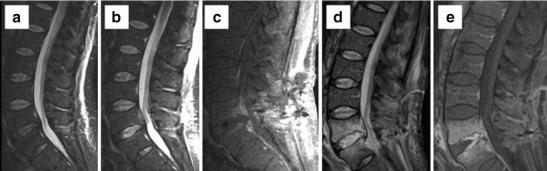

Lumbar spine surgery for spinal stenosis is a frequently performed procedure and was the fastest growing type of surgery in the US from 1980 to 2000. With increasing surgical invasiveness, postoperative complications also tend to be higher. Cross-sectional imaging techniques (CT and MRI) are more sensitive than radiographs and play an increasingly important role in evaluation of patients with lumbar spine surgery. Their use in patients with metallic implants is somewhat limited by artefacts, which can obscure pathology and decrease accuracy and reader confidence. Metal artefact reduction techniques have been developed, which can significantly improve image quality and enable early detection of postoperative complications. Complications can occur throughout postoperative course. Early complications include hardware displacement, incidental durotomy, postoperative collections-most commonly seroma, and less likely haematoma and/or infection. Incidental durotomy with CSF leak causing intracranial hypotension has characteristic MR brain findings and diagnosis of occult leak sites have been improved with use of dynamic CT myelography. Haematomas, even when compressing the thecal sac, are usually asymptomatic. Early infection, with nonspecific MR findings, can be diagnosed accurately using dual radiotracer studies. Delayed complications include loosening, hardware failure, symptomatic new or recurrent disc herniation, peri-/epidural fibrosis, arachnoiditis, and radiculitis.

• CT and MRI play an increasingly important role in evaluation of patients with lumbar spine surgery • Complications can occur throughout the postoperative course and early detection is critical • Artefact reduction techniques can improve image quality for early and improved detection of complications.